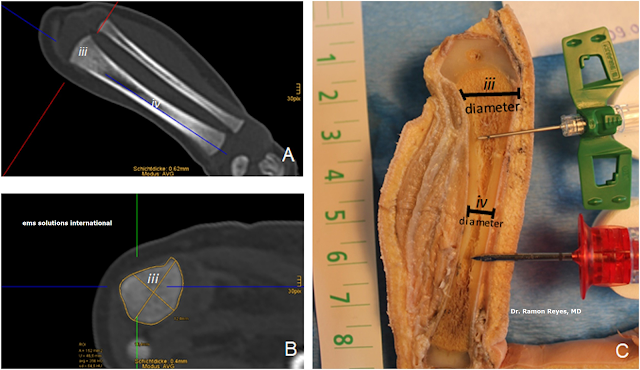

Figura 3. A+C) Corte frontal y B) transversal de tibia izquierda en cadáver de recién nacido a término (39+5GA). Los diámetros y circunferencias de la corteza intacta se determinaron a partir de las imágenes de TC de ventana de hueso (A+B) a la altura de la cabeza del peroné y tuberositas tibiae (iii) (10 mm de la capa de cartílago-hueso) y tibial diafisaria (iv). ). Una aguja EZ-IO® IO roja PD 15G (1,8 mm de diámetro) y una aguja verde butterfly® 21G (0,8 mm de diámetro) indican los tamaños relativos.

Fig. 3. A + C) Frontal and B) transverse section of the left tibia in a term newborn cadaver (39 + 5GA). The diameters and circumferences of the intact cortex were determined from the bone window CT-images (A + B) at the hight of the fibular head and tuberositas tibiae (iii) (10 mm from the cartilage-bone layer) and diaphyseal tibial (iv). A red EZ-IO® IO needle PD 15G (1.8 mm diameter) and a green butterfly® 21G (0.8 mm diameter) needle indicate relative sizes.